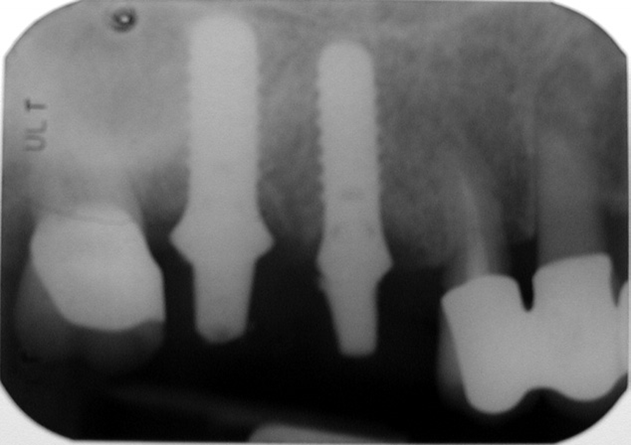

Při ztrátě molárů a premolárů v horní čelisti a jejich náhradě implantáty se často setkáváme s nedostatečnou vertikální nabídkou kosti pod čelistní dutinou, často doprovázenou i nedostatečnou horizontální nabídkou a sníženou kvalitou kosti

(v oblasti 2. premoláru v 50%, v oblasti moláru až v 80% případů nedostatečná kostní nabídka)

Od roku 1985 je tento problém řešen augmentační operací nazývanou sinus lift.

Jedná se o vyzvednutí membrány, která čelistní dutinu vystýlá, pod vyzvednutou membránou vznikne kapsa, kam se umístí augmentační materiál, do kterého se zavedou implantáty.

Vhojení implantátů se při této operaci prodlužuje na 6-12 měsíců.